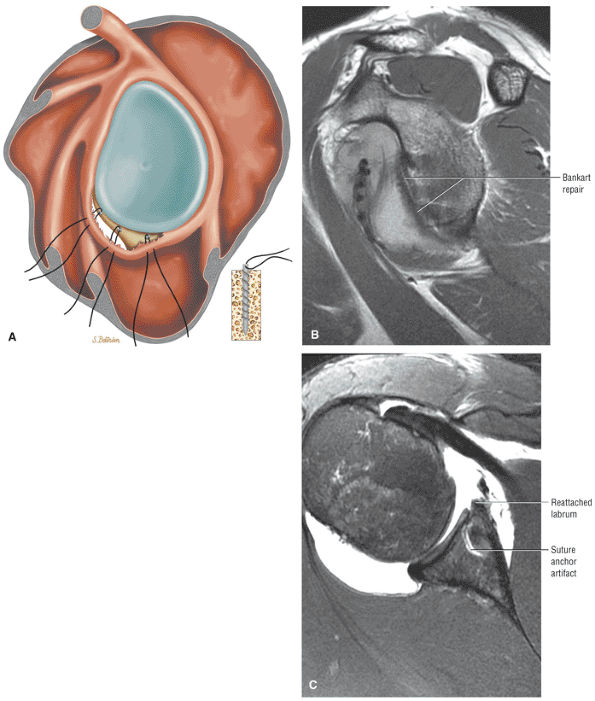

Postoperative evaluation of repaired labral capsular structures and/or strictures, recurrent rotator cuff tears or partial tears, and displaced hardware

ABER (abduction external rotation) images in conjunction with MR arthrography are helpful in evaluating the postoperative labrum and nondisplaced (e.g., Perthes) labral tears.